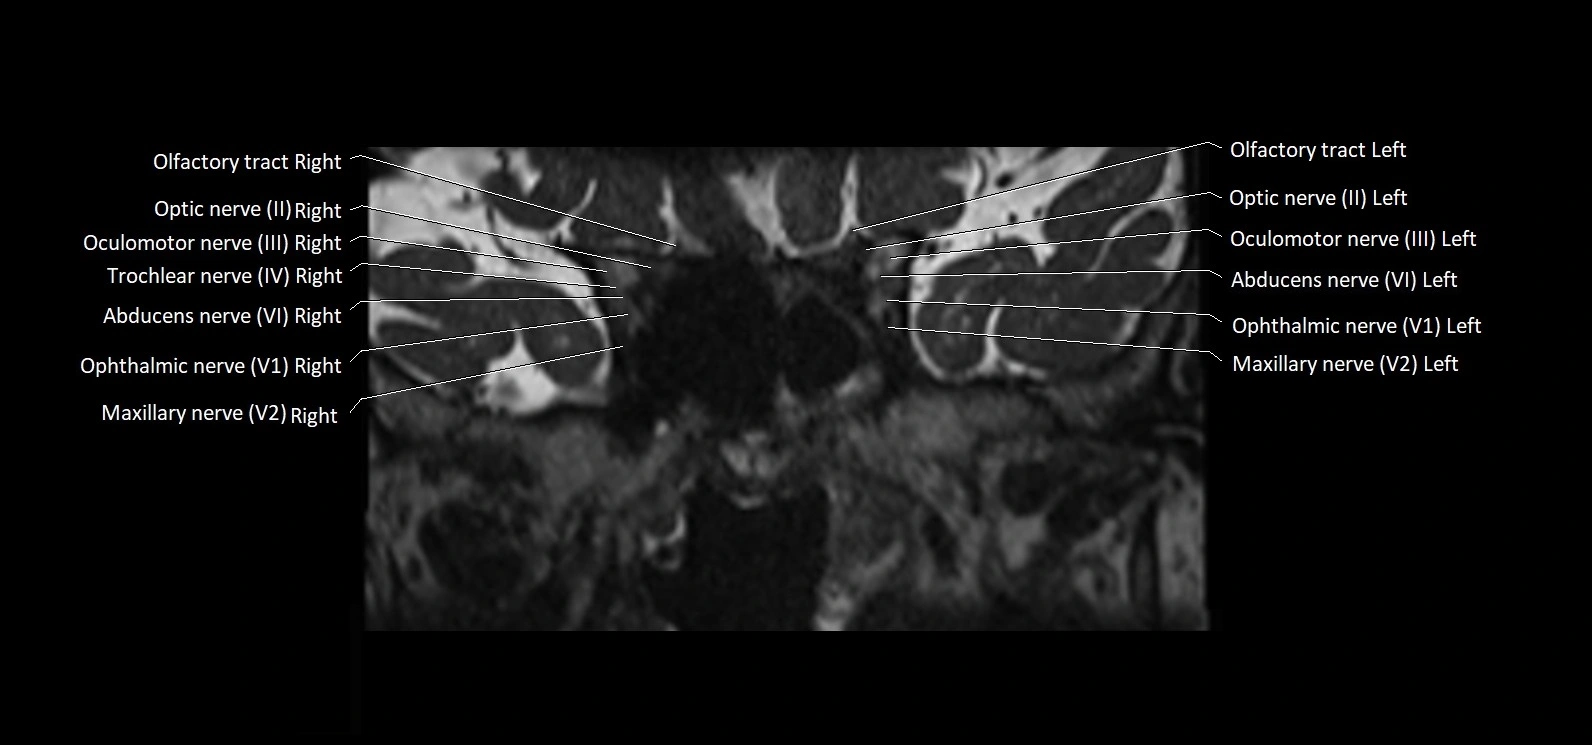

MRI Appearance

• The abducens nerve is a small, thin, linear structure

• Best visualized on high-resolution T2-weighted 3D MRI sequences (e.g., FIESTA or CISS)

• Seen as a hypointense (dark) line running from the brainstem at the pontomedullary junction, traversing the prepontine cistern, and entering Dorello’s canal under the petrosphenoidal ligament, then into the cavernous sinus, and finally the orbit

• May be challenging to visualize in standard MRI due to its small size

• Pathology may be inferred by absence, displacement, or enhancement of the nerve